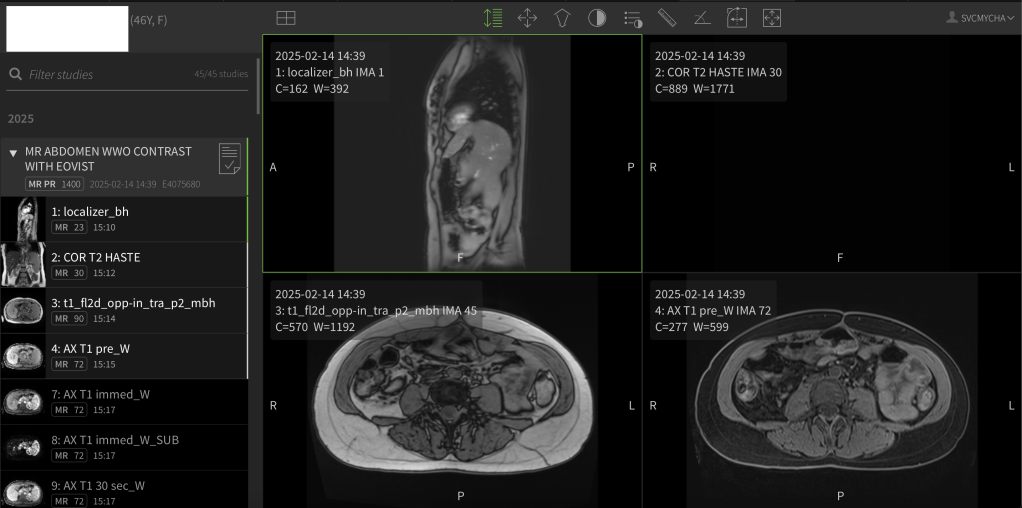

This past week I had an echocardiogram, bloodwork, an MRI, and then an appointment with my oncologist to discuss all the results. Verdict: my various tumors are growing so slowly they are considered “stable”, and although I do have new tumors, they are still quite small. In Cancer World, that is all GREAT NEWS, and I’m feeling lucky and appreciative!!

One new possible concern is my heart. “Carcinoid Heart Disease” (blood sloshing around in the right side of the heart because NETs are causing plaque-like deposits on the valve) is a real concern for patients with neuroendocrine cancer. This week I had a Pro-BNP blood test to see how stressed out my heart is, and my level is elevated compared to last year. Also, on my recent echocardiogram I show “mild” tricuspid regurgitation, which is an increase from the “trace” tricuspid regurgitation I showed a year ago. So, my oncologist is staying on the right side of caution and is looping in a cardiologist to my case.

1) I have a referral to see a cardiologist and get a “MRI with elastography” for my heart.

3) In August I’ll have another MRI and an appointment with my oncologist.